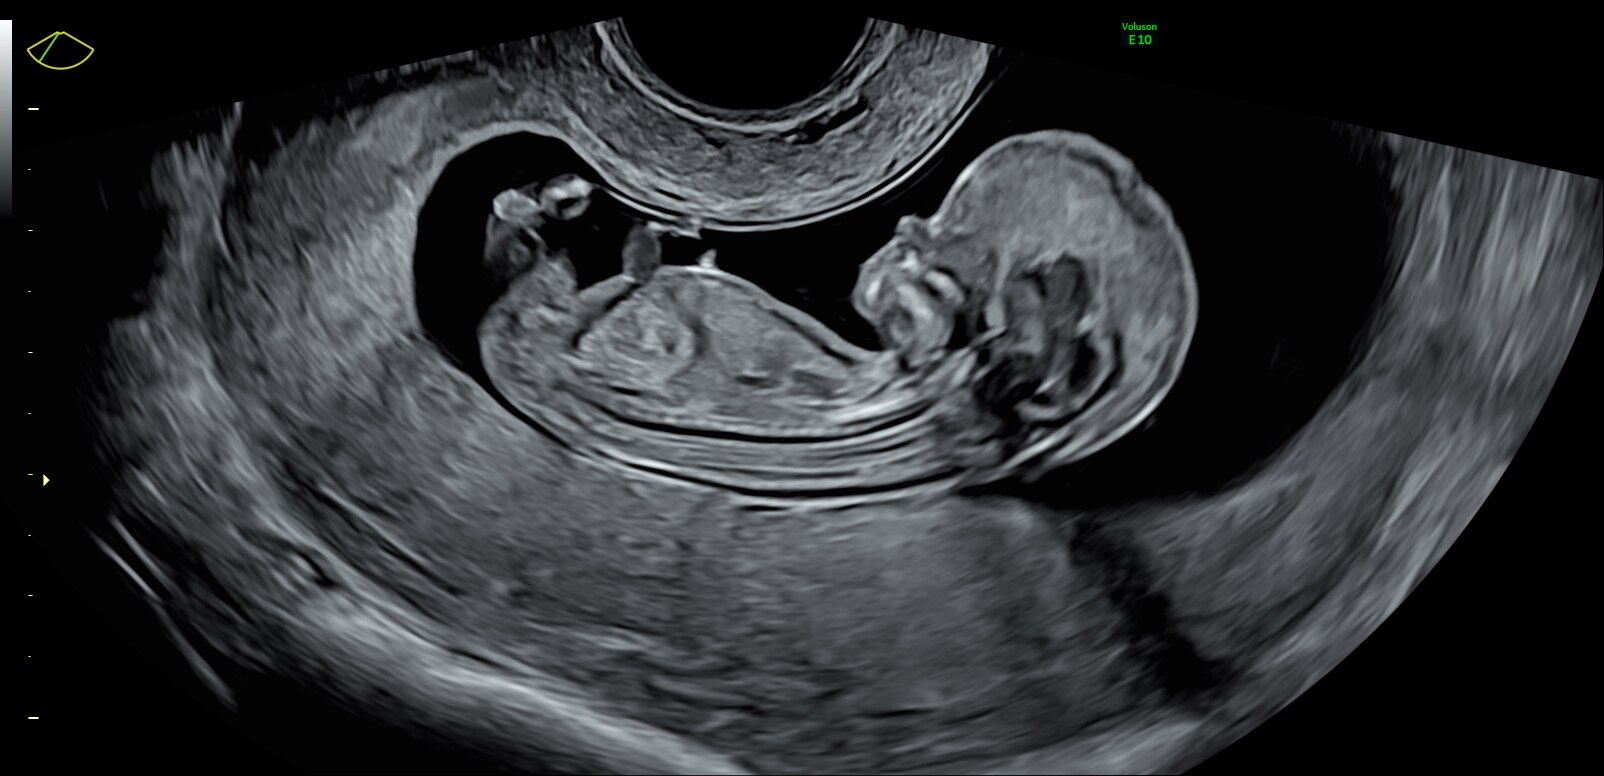

Fetus with HDlive™ generated with SonoRenderlive